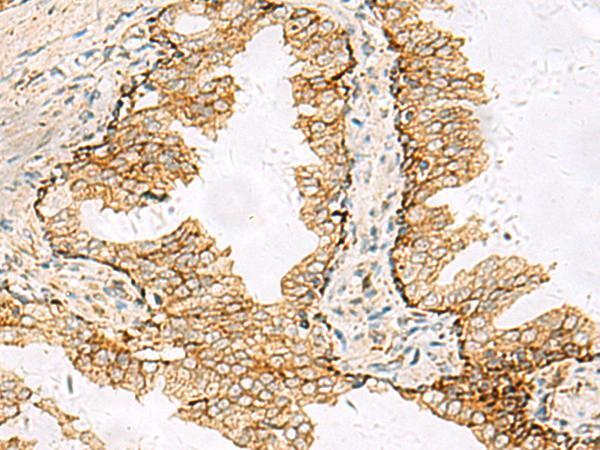

- Immunohistochemistry of paraffin-embedded Human prost at e cancer tissue using SH3YL1 Polyclonal Antibody at dilution of 1:55(×200)

- Immunohistochemistry of paraffin-embedded Human liver cancer tissue using SH3YL1 Polyclonal Antibody at dilution of 1:55(×200)